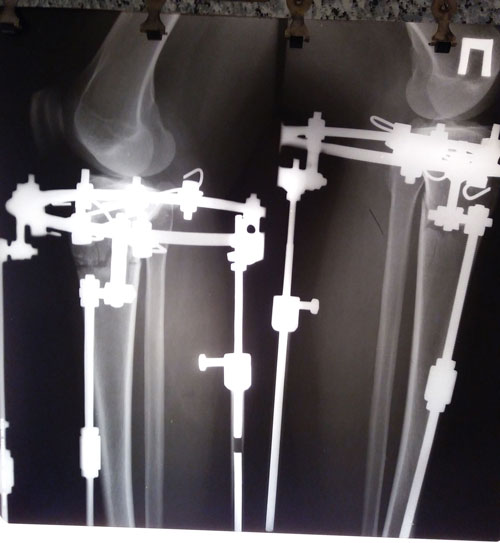

Исходник - 39 лет. Астана.

Дата операции 17.10.2017г.